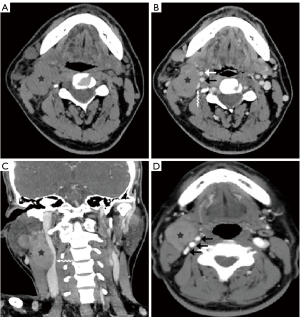

Paragangliomas have characteristic CT and MRI appearances based on their hypervascularity. They are usually homogeneously or heterogeneously hyperdense or hyperintense after contrast enhancement, with incorporation of adjacent arteries on CT and MRI (Figures 10-12) (12). On MRI, serpentine and punctate areas of signal void representing high vascular flow are interspersed with areas of high signal intensity caused by slowly flowing blood. This “salt-and-pepper” pattern is seen in all lesions greater than 2 cm in maximal dimension (Figure 11) (23-25). Carotid body tumors (paragangliomas of the carotid body) splay the ICA and the external carotid artery (ECA) and may encase the ICA and ECA (Figure 10), whereas vagal paragangliomas displace both ICA and ECA anteromedially, separating these vessels from the IJV (Figure 11). Paragangliomas may be multicentric and can manifest as unilateral or bilateral lesions, either simultaneously or sequentially. Only a very low percentage of 3% of paragangliomas will undergo malignant transformation (25). The presence of local lymph node involvement, distant metastases, or extensive local invasion will establish the malignancy of a paraganglioma.

In the past, digital subtraction angiography (DSA) played an important role as a first-line imaging investigation for paragangliomas (26). However, such an invasive method is reserved for those few patients whose diagnosis, after sectional imaging, remains inconclusive, or preoperative embolization. DSA, and sometimes computed tomography angiography (CTA), will show feeding arteries, such as the ascending pharyngeal artery (the artery of the paraganglioma) (Figure 12) and occipital artery (27). DSA also shows intense staining of the tumor and a rapid venous drainage.